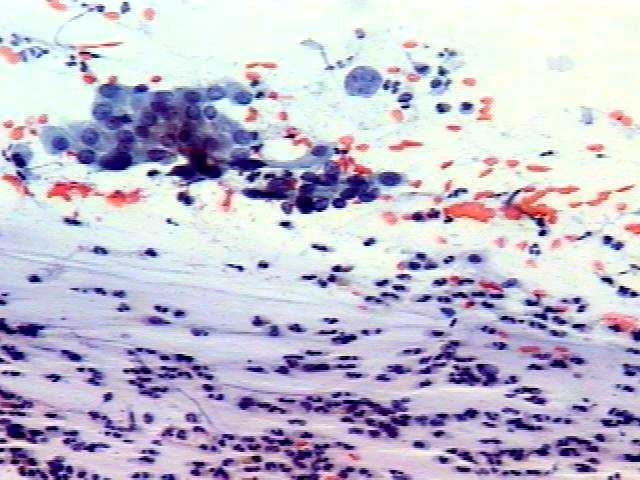

1